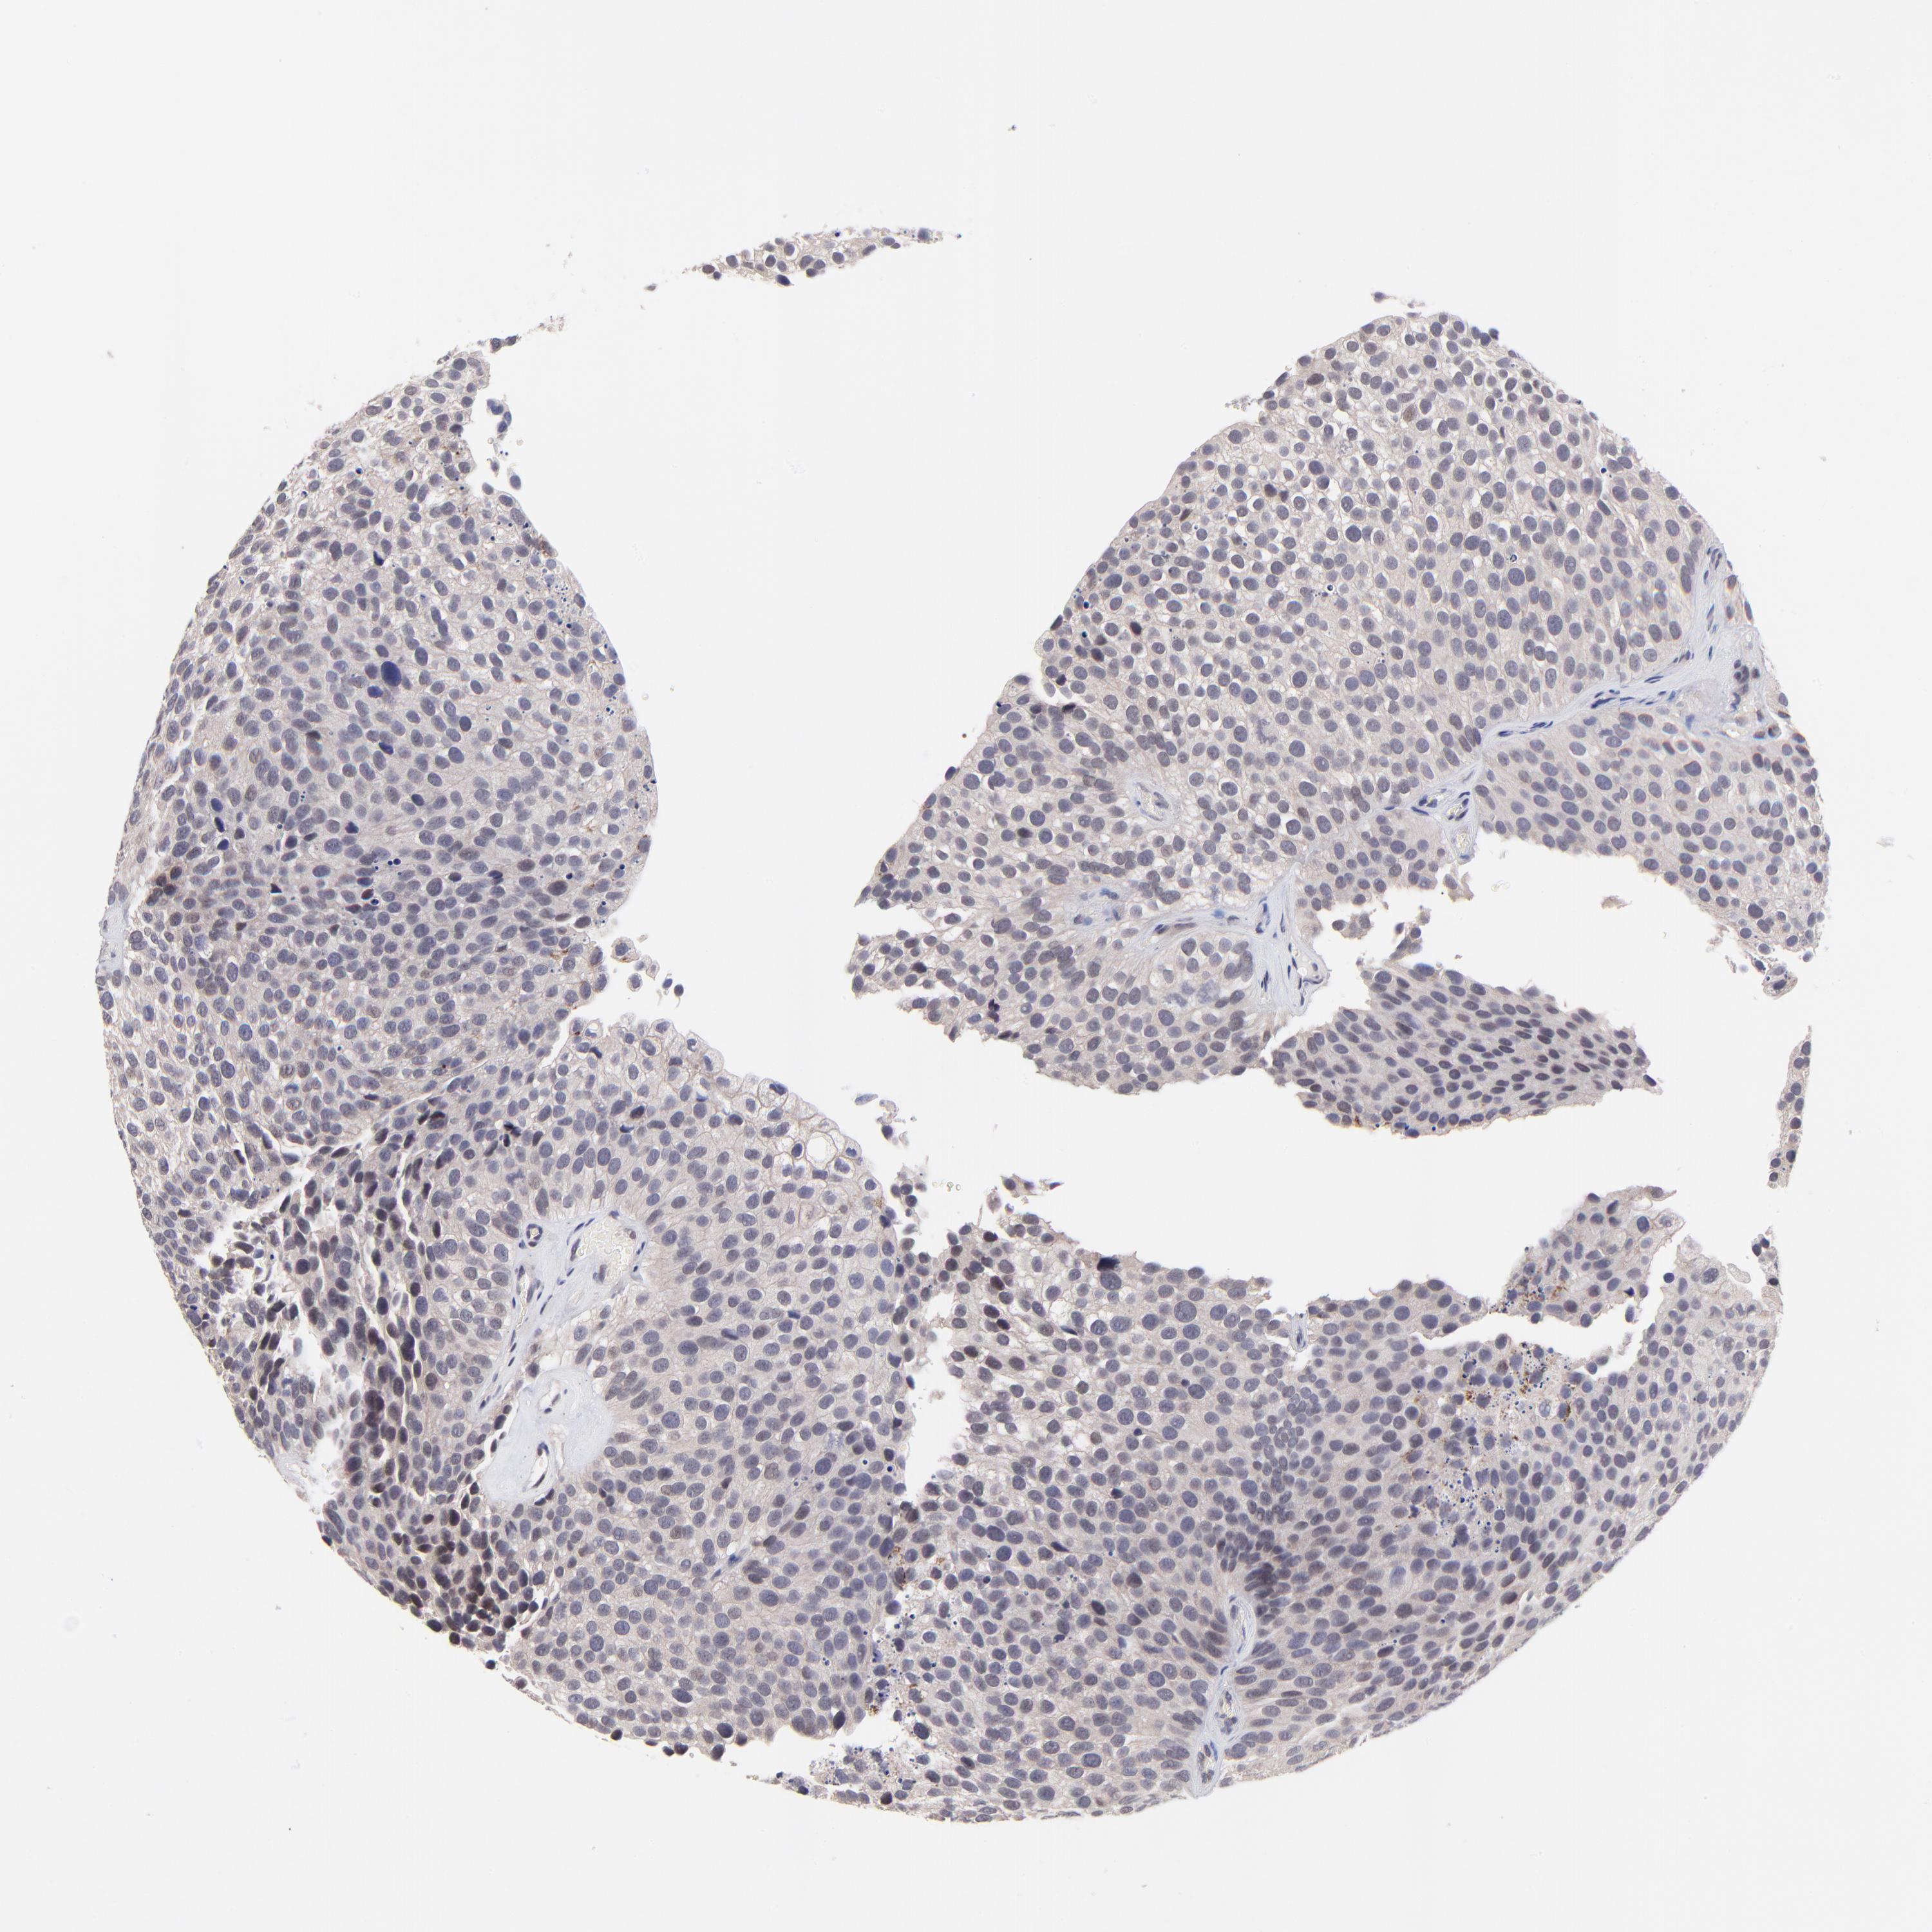

UROTHELIAL CANCER - Protein expressioni

A mouse-over function shows sample information and annotation data. Click on an image to view it in a full screen mode. Samples can be filtered based on level of antibody staining by selecting one or several of the following categories: high, medium, low and not detected. The assay and annotation is described here.

Antibody stainingi

Antibody staining in the annotated cell types in the current human tissue is reported as not detected, low, medium, or high, based on conventional immunohistochemistry profiling in selected tissues. This score is based on the combination of the staining intensity and fraction of stained cells.

Each image is clickable and will lead to virtual microscopy that enables deeper exploration of all samples and also displays staining intensity scores, fraction scores and subcellular localization as well as patient and tissue information for each sample.

Antibody HPA003203

Staining

High

Medium

Low

Not detected

Intensity

Strong

Moderate

Weak

Negative

Quantity

>75%

75%-25%

<25%

None

Location

Nuclear

Cytoplasmic/membranous

Cytoplasmic/membranous,nuclear

Urothelial carcinoma, High grade